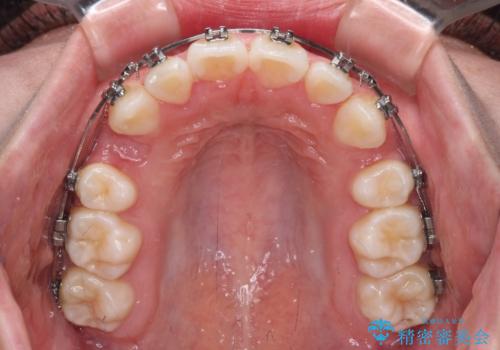

- 歯のデコボコや八重歯、クロスバイトを気にして来院された患者様です。

上下左右第一小臼歯4本を抜歯し、ワイヤー装置にて歯列を整え、さらには少しでも口元を引っ込めるよう矯正治療を行うこととしました。

- メタルブラケット